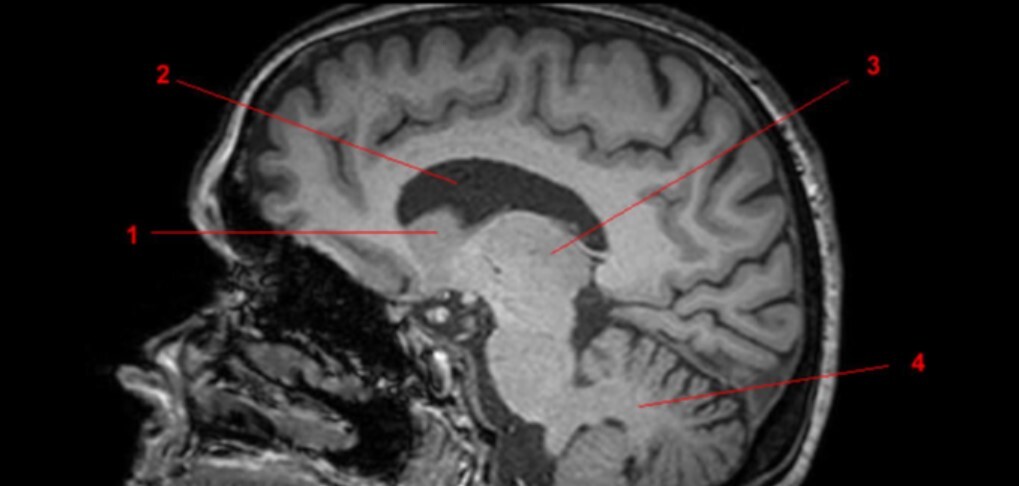

14

Label 1-9

A

1=Rostrum (CC)

2-Genu (CC)

3-Body (CC)

4=Splenium (CC)

5=Lateral ventricle

6=Thalamus

7=Midbrain

8=Pons

9-Medulla oblongata

15

Label 10-18

10-4th ventricle

11=Cerebellum

12=Cisterna Magna

13=Basilar artery

14=Clivus

15-Mamillary body

16=Optic chiasm

17=Infundibulum

18=Occipital bone

16

Label 19-27

19=Sphenoid sinus

20=Quadrigeminal cistern

21=Occipital lobe

22-Frontal lobe

23-Parietal lobe

25-Cerebral aqueduct

26-Frontal bone

27-Spinal canal